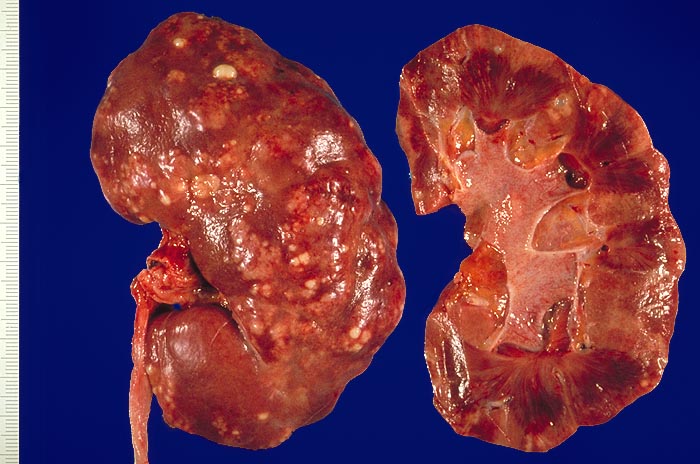

Symptomatik:

Die Patienten haben Fieber über 38°C, Flankenschmerzen, klopfschmerzhafte Nierenlager, Übelkeit, Erbrechen und ev. einen paralytischen Ileus. Pollakisurie und Dysurie können fehlen.

Komplikationen:

Als gefürchtete Komplikation kann sich eine Urosepsis (und ev. septischer Schock) meist mit gram negativen Keimen entwickeln. Besonders gefährdet sind Patienten mit Harnwegsobstruktion, Dauerkatheter, Zystennieren, Schwangerschaft, Diabetes mellitus und Immunsuppression.

Prognose:

Vor allem bei obstruktiver Ursache ist die Erkrankung potentiell lebensgefährlich.